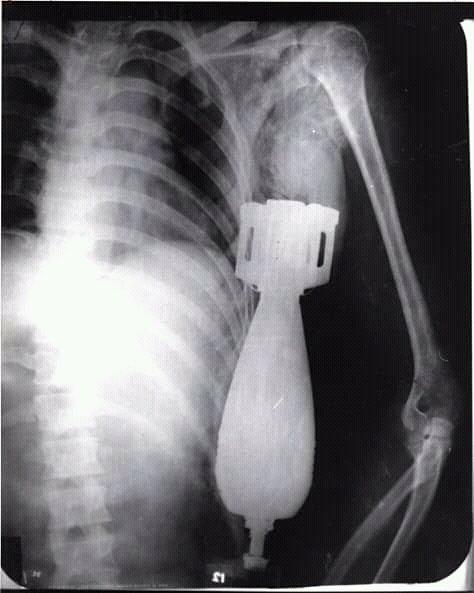

阮文龙的X光照

之后,阮文龙的战友小心翼翼地将他送到了岘港海军医院,美军军医哈利·丁斯摩尔(Dr.Harry Dinsmore)为其进行外科手术。由于这枚炮弹仍有爆炸的可能,因此哈利·丁斯摩尔疏散了医院的人群,并让其他士兵在手术室外用沙袋构筑了防爆工事。当一切处理妥当后,哈利·丁斯摩尔为阮文龙拍摄了X光图片,最终确定这枚炮弹没有卡在骨头上,也没有伤及阮文龙的脏器,随后哈利·丁斯摩尔决定立即对阮文龙展开外科手术。